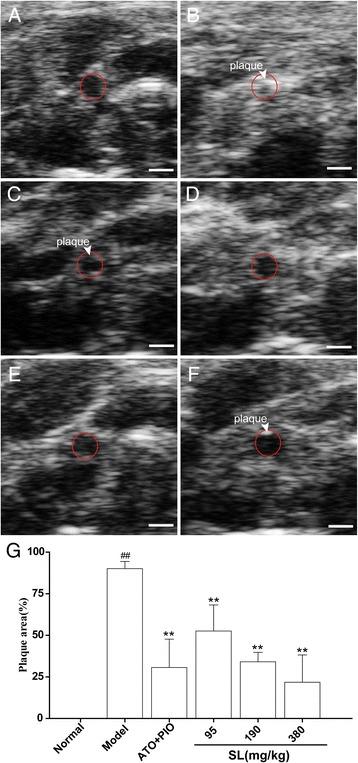

This study directly and dynamically investigated the effects of SL extract (i.e., a combination of Radix Salviae miltiorrhizae and Andrographis paniculata extract) on plaque progression in vivo by high resolution ultrasound biomicroscopy (UBM).

An atherosclerosis model was established by placing a perivascular collar on the right common carotid artery in apolipoprotein E-deficient (ApoE) mice. Thickness, plaque area and local blood flow were observed by UBM, pathological changes were observed by histochemical staining, and lipid levels were measured by respective commercially available kits.

Compared with the model group, the SL extract groups showed reduced wall thickness of the aortic arch (GC: P = 0.001, P = 0.002, and P < 0.001; LC: P < 0.001, P < 0.001, and P < 0.001; BC: P = 0.027, P = 0.017, and P = 0.003; respectively), which presented with retarded plaque progression of the cartoid artery with concordantly increased blood flow (P = 0.002 and P < 0.001) as visualized in vivo by UBM. Histological analysis confirmed the reduction of carotid atherosclerosis.

The SL extract inhibited the formation of atherosclerotic plaques in an ApoE mice model by UBM analysis, and did so by effects that ameliorated local blood flow and improved blood lipid levels.